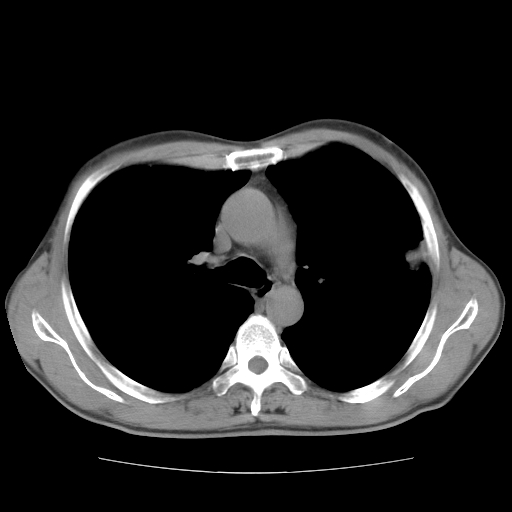

以下是引用drzhang8888在2008-11-20 22:20:00的发言:[br]密集的短毛刺,血管集束,胸膜凹陷,周边型肺癌可能性大,另双肺多发磨玻璃影,考虑感染

以下是引用流浪星在2008-11-20 22:28:00的发言:[br]左肺上叶近外围区见一类圆形结节影,毛刺征、胸膜尾征阳性,临近肺组织见多发渗出灶。考虑1,炎症性病变。 2.周围性肺癌。建议抗炎治疗后复查。